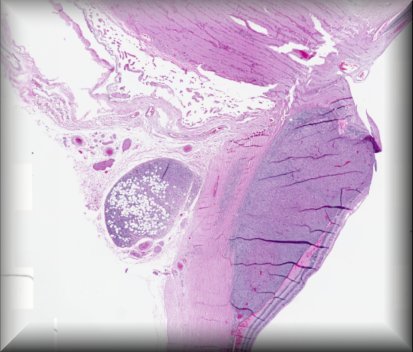

Luis Alfaro (Valencia): 53 year-old-man with a corneal transplant 3 years ago with poor evolution, who underwent retransplantation after being treated with amniotic membrane graft. |